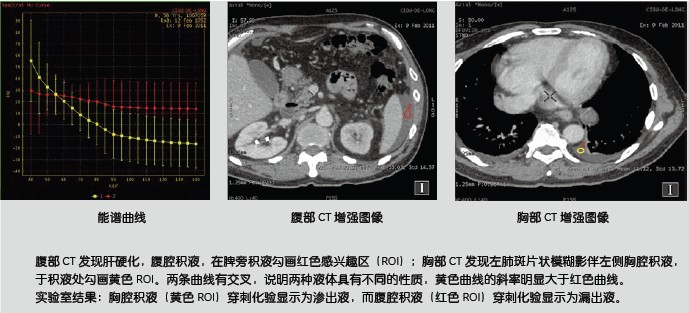

新技術(shù)介紹三:物質(zhì)分離與定量

MD尿酸像 MD鈣基像 尿酸與骨質(zhì)分離

痛風(fēng)由于尿酸結(jié)晶體沉積在人體組織所致,而假性痛風(fēng)是由于磷酸鈣鹽沉積所致。如果在關(guān)節(jié)內(nèi)不進行穿刺活檢無法評估尿酸結(jié)晶存在。寶石能譜CT物質(zhì)分離像可以提示痛風(fēng)或者假性痛風(fēng)存在,并加以鑒別。